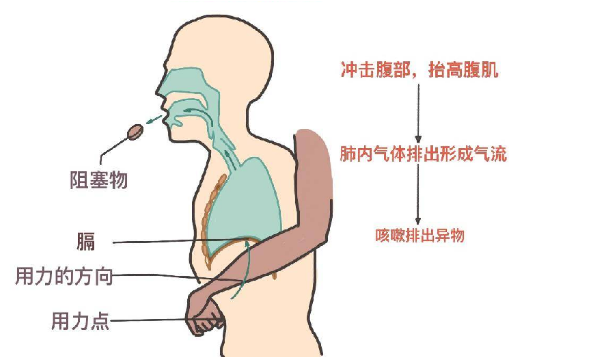

海姆立克急救法更新了:先拍5次背 再做“剪刀石头布”